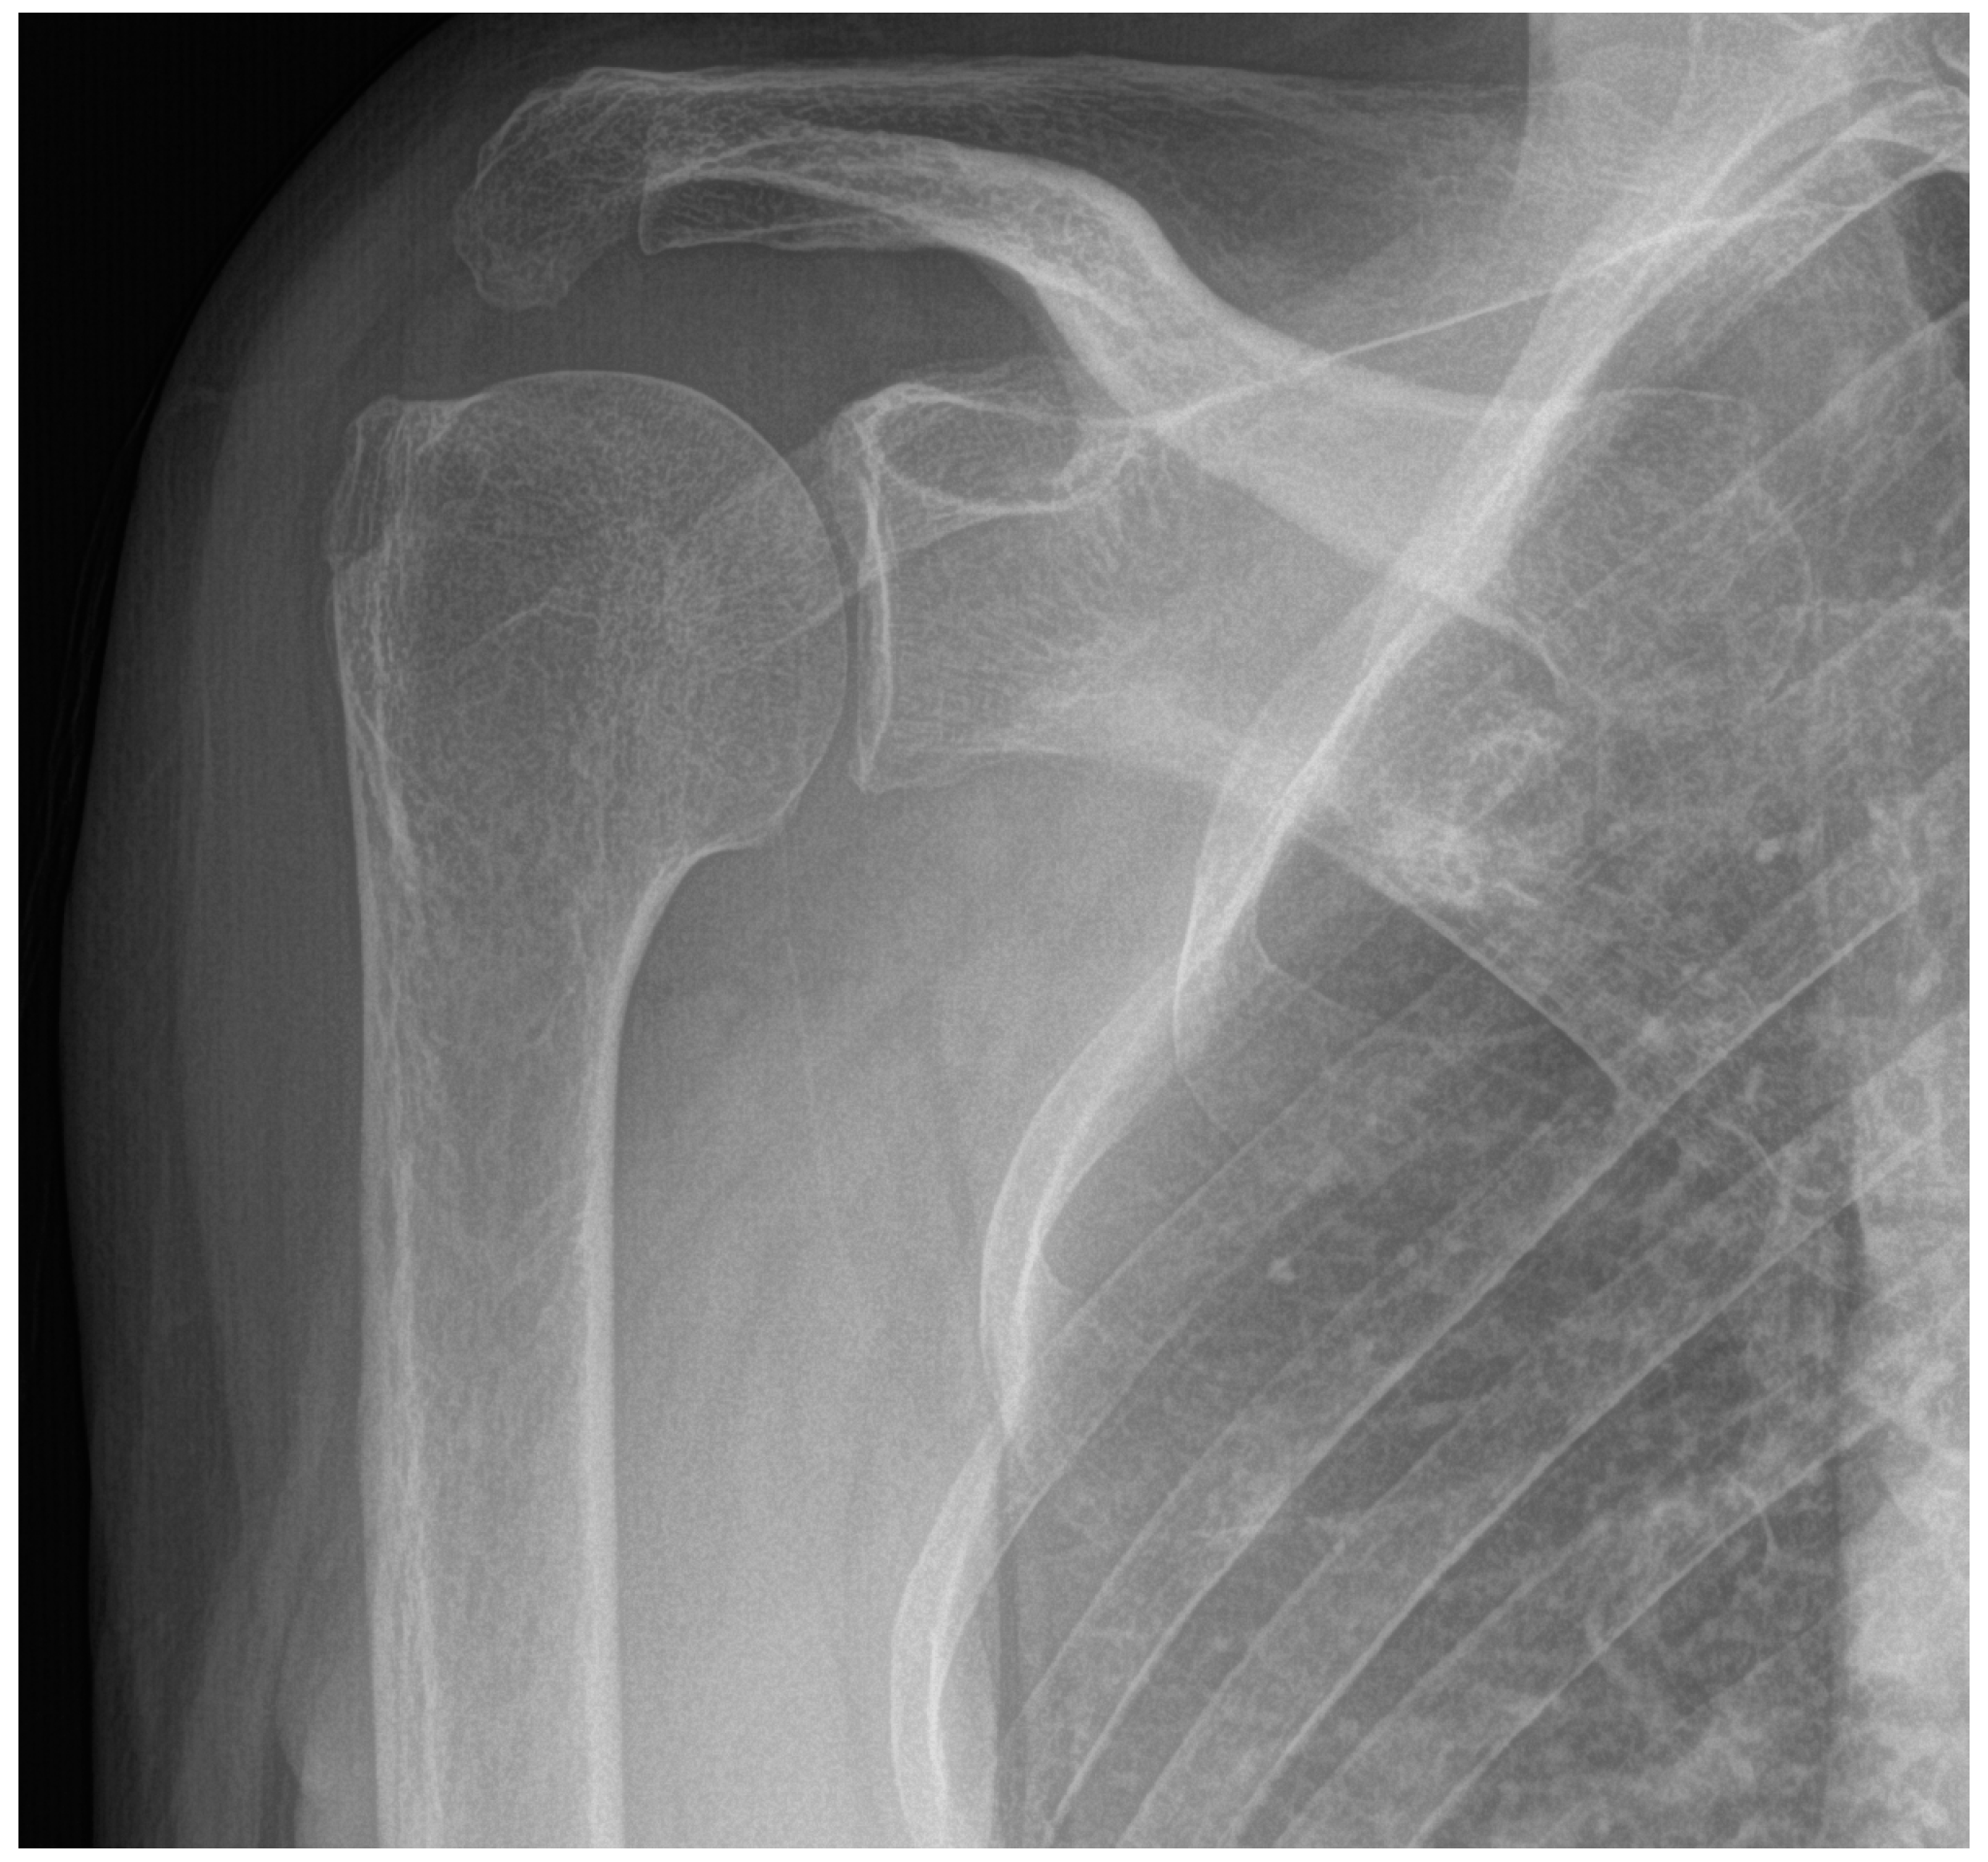

2. Detailed Case Description